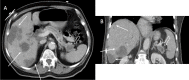

Annotated contrast-enhanced CT of the abdomen and pelvis at the level of the pelvis in bone windows with axial images showing an expansile, lytic lesion within right sacral Ala (closed arrow) and two expansile lytic lesions within right iliac bone (open arrows).